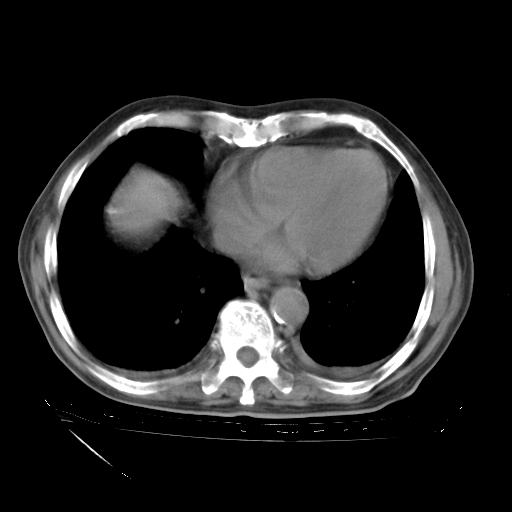

甲强龙80mg/日+抗结核治疗(异烟肼+利福霉素+乙胺丁醇)10天。复查肺部CT。

治疗10天肺部CT

补充下:5月9日胸部CT:似乎已见双下肺胸腔积液了,鉴于目前有下肢水肿,肝功示:白蛋白低,应注意多浆膜腔积液(漏出液可能大?),需注意!